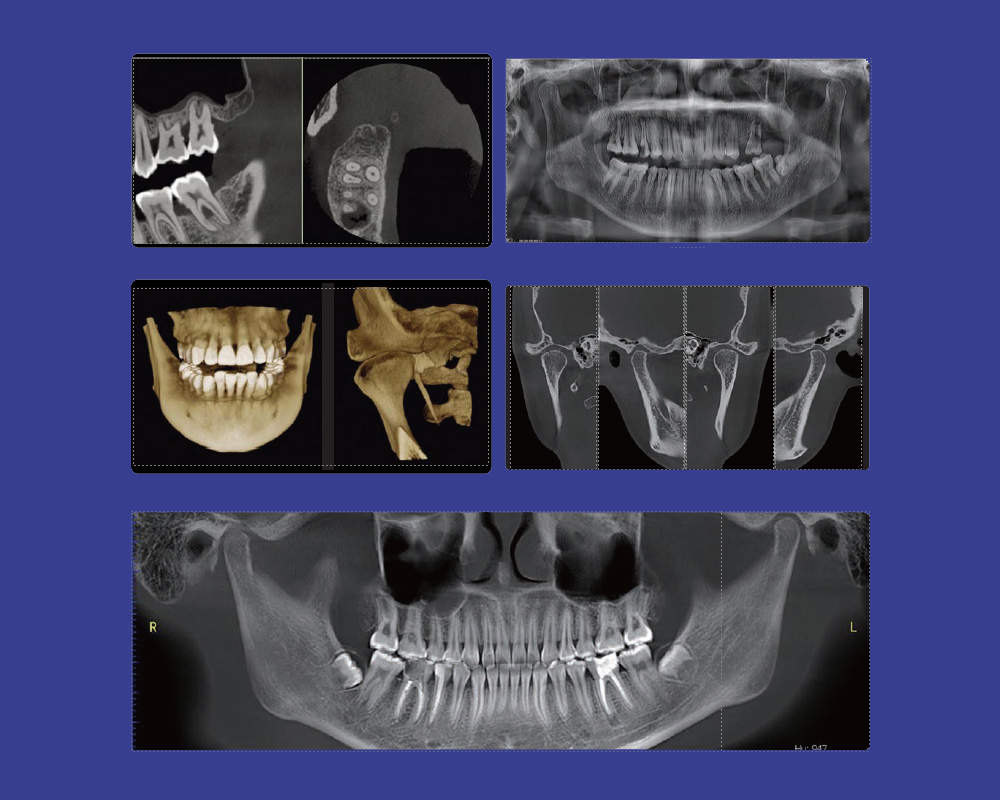

Smart3D-X es un producto CBCT dental multifuncional de última generación, que combina funciones de TC, panorámica, radiografía cefalométrica (opcional) y escaneo de modelos (opcional), y ha ganado el premio de diseño internacional IF.

• Tomografía computarizada de 360°, proyecciones masivas y algoritmos exclusivos y avanzados desarrollados por nosotros. (Imágenes de alta calidad)

• Imágenes 3D de gran campo de visión

• Resolución súper alta: 2.4lp/mm

• Velocidad súper rápida: 13 seg. de tiempo de escaneo

• Eliminación de artefactos metálicos únicos